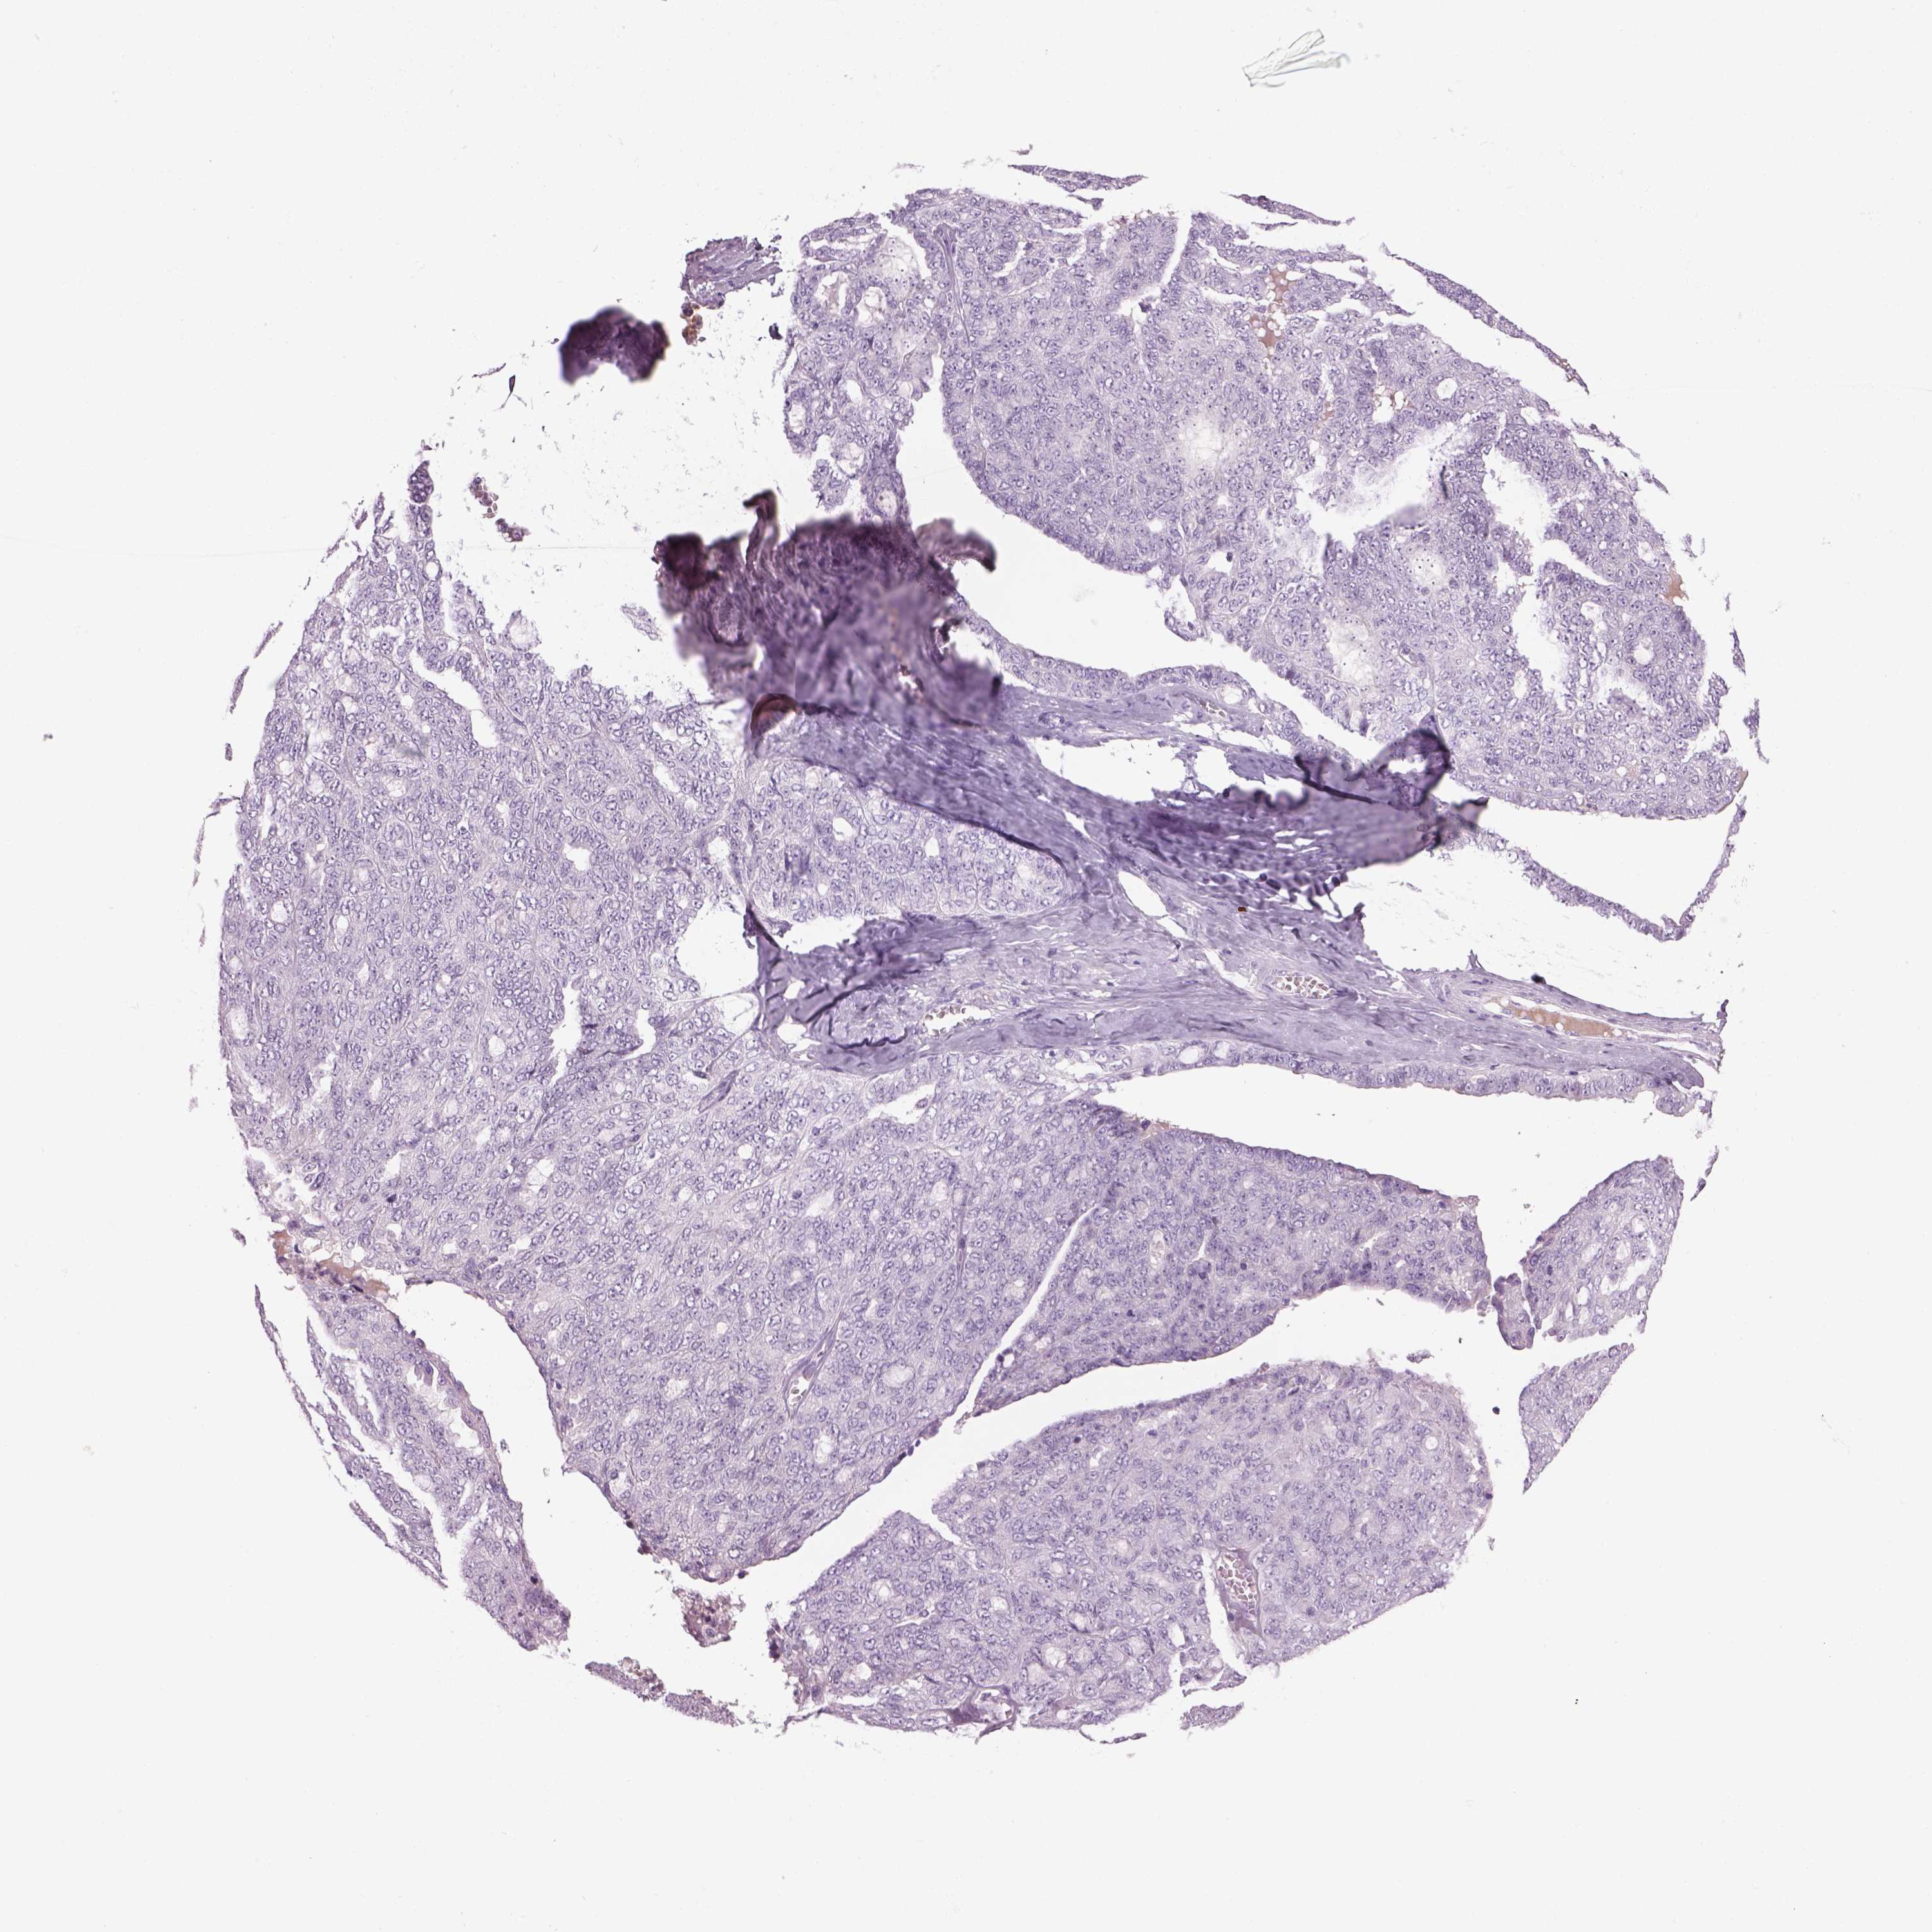

OVARIAN CANCER - Protein expressioni

A mouse-over function shows sample information and annotation data. Click on an image to view it in a full screen mode. Samples can be filtered based on level of antibody staining by selecting one or several of the following categories: high, medium, low and not detected. The assay and annotation is described here.

Note that samples used for immunohistochemistry by the Human Protein Atlas do not correspond to samples in the TCGA dataset.

Antibody stainingi

Antibody staining in the annotated cell types in the current human tissue is reported as not detected, low, medium, or high, based on conventional immunohistochemistry profiling in selected tissues. This score is based on the combination of the staining intensity and fraction of stained cells.

Each image is clickable and will lead to virtual microscopy that enables deeper exploration of all samples and also displays staining intensity scores, fraction scores and subcellular localization as well as patient and tissue information for each sample.

Antibody HPA073761

Cystadenocarcinoma, serous, NOS

Cystadenocarcinoma, mucinous, NOS

Carcinoma, endometroid